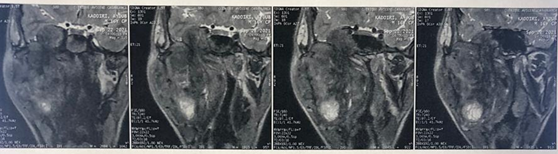

The patient then underwent MRI of the face, which

revealed a voluminous, largely necrotic tissue lesion in the right

infra-temporal fossa, measuring 94 mm in long axis, with irregular contours in

T1 hyposignal, discrete T2 hyper signal, diffusion hypersignal with low ADC,

intensely and heterogeneously enhancing after injection of gadolinium,

delineating areas of necrosis.

Superiorly and medially, it infiltrates the right parapharyngeal space

and the nasopharynx, partially filling its lumen. Superiorly and laterally, it

compresses the homolateral parotid gland and reaching the subcutaneous soft

tissue (Figure 3).

Figure 7: MRI on coronal section

showing the tumor that comes into contact the floor of the orbit

Figure 8: MRI on coronal section

showing the tumor infiltrating the base of the skull, and the homolateral temporal lobe